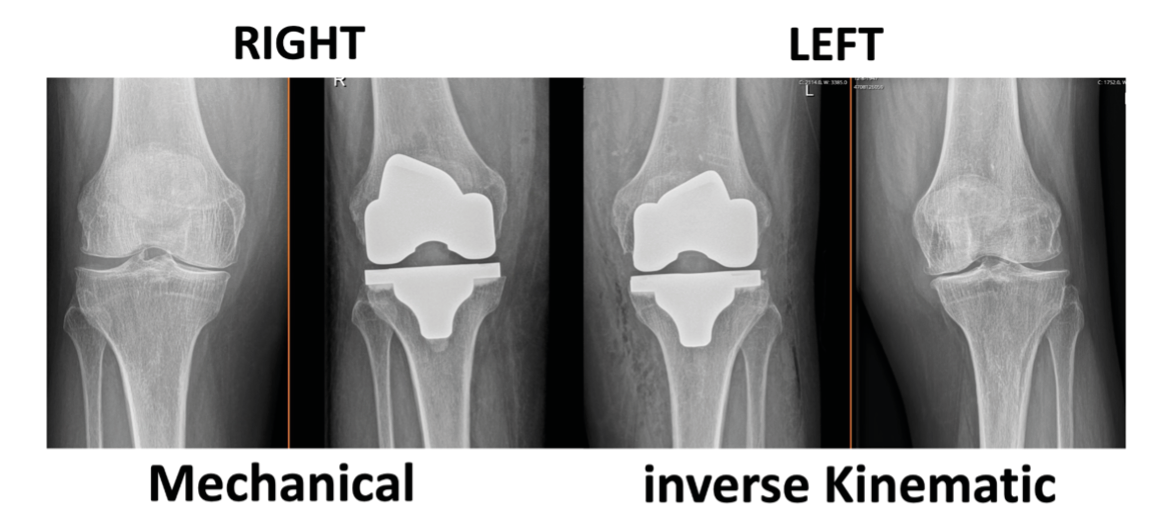

This issue's clinical contributions span alignment strategies and implant selection in major joint reconstruction. In total knee arthroplasty, one article examines TKA in extraarticular deformities managed through intraarticular correction without increased constraint, while a second introduces inverse kinematic alignment as a framework for personalized alignment. Shoulder arthroplasty is addressed through an assessment of the stemless shoulder implant. A further study evaluates whether surgical approach influences canal fill of the femoral component in THA, contributing to the evidence base on technique-dependent outcomes.